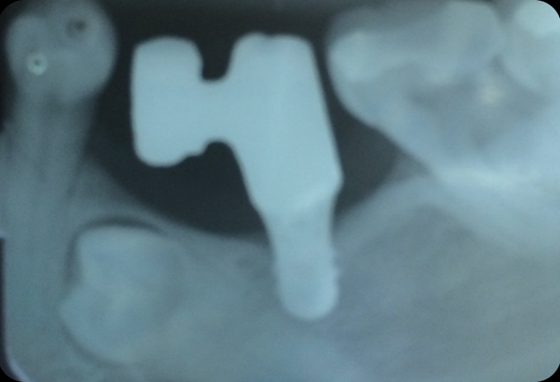

The implant was installed with local anesthesia in the region of tooth 35 and after 60 days a metal-clay prosthesis was installed encompassing tooth 35 over the implant and a cantilever replacing tooth 34. The teeth were placed in conventional occlusion.

In the 3-year control, it was possible to observe the maintenance of the bone level of the peri-implant tissue and the integrity of the tooth that remains included. No prosthetic complications were encountered during this period (figure 3).

Figure 3: Periapical radiograph after the period of implant osseointegration and prosthetic rehabilitation.